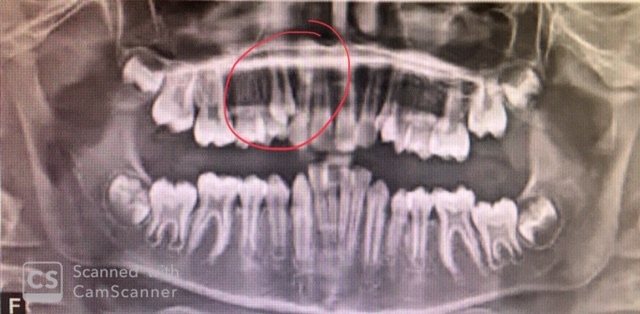

Identify the age of this patient

Age 8